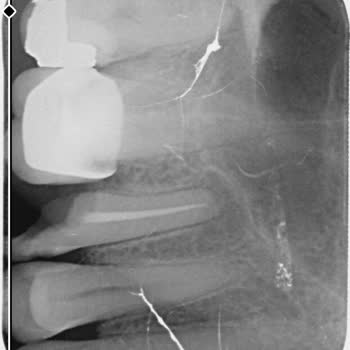

Ataşehir Ağız ve Diş Sağlığı Hastanesi'nde kanal tedavisi olmam gereken dişime 'derin dolgu ile kurtarırız' diyerek derin dolgu yapan Doktor *** nedeniyle sürekli dişimde apse oluşmaya başladı. Kontrole gidip şikayetimi söylediğimde Endodonti bölümüne, yani kanal tedavisi olmam gerektiği söylendi. B...